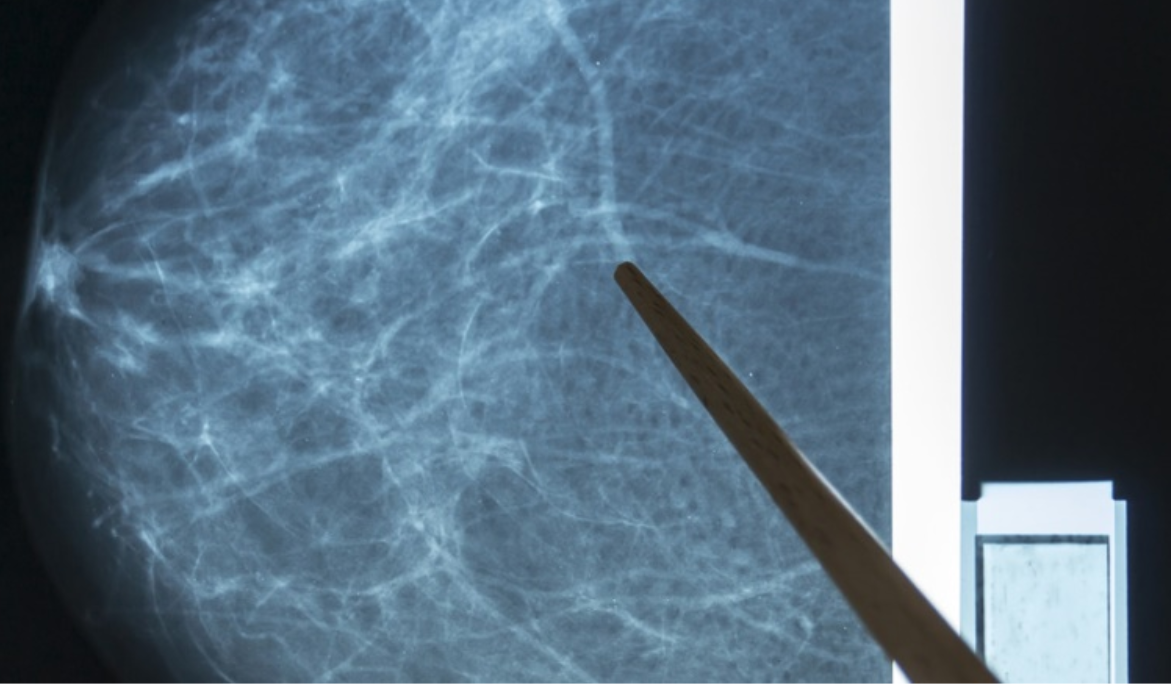

Los sistemas de detección asistida por computadora (CAD) utilizan una imagen mamográfica digitalizada que puede obtenerse de una mastografía de película convencional o de una mamografía adquirida digitalmente. El software de la computadora busca áreas anormales de densidad, masa o calcificación que pueden indicar la presencia de cáncer. El sistema CAD resalta estas áreas en las imágenes, alertando al radiólogo sobre la necesidad de análisis adicionales. La mastografía sigue siendo el estándar de oro para la detección del cáncer de seno en etapa temprana. El objetivo de la mastografía es la detección temprana del cáncer de seno, a través de la detección de masas y / o microcalcificaciones (pueden aparecer pequeños trozos de calcio dentro de los tejidos blandos del seno).

En mujeres con tejido mamario fibroquístico denso, la masa mamaria se muestra blanca en una mastografía; los tumores también son blancos. Con las mastografías digitales, el radiólogo puede manipular el contraste de las imágenes, haciéndolas más oscuras o más claras, lo que permite identificar las masas. Las imágenes también se pueden ampliar en la computadora para enfocarse en áreas de alerta.